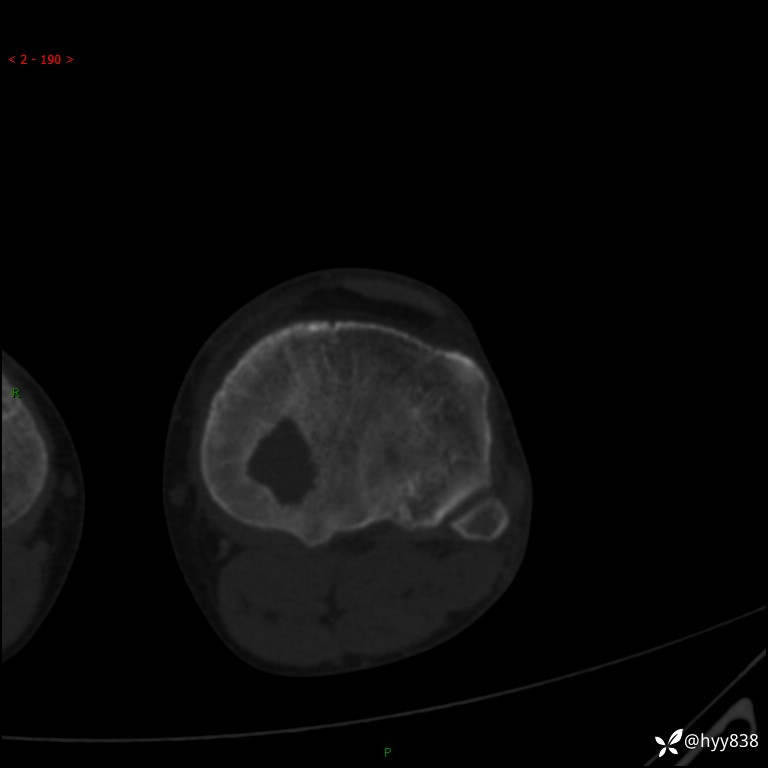

CT